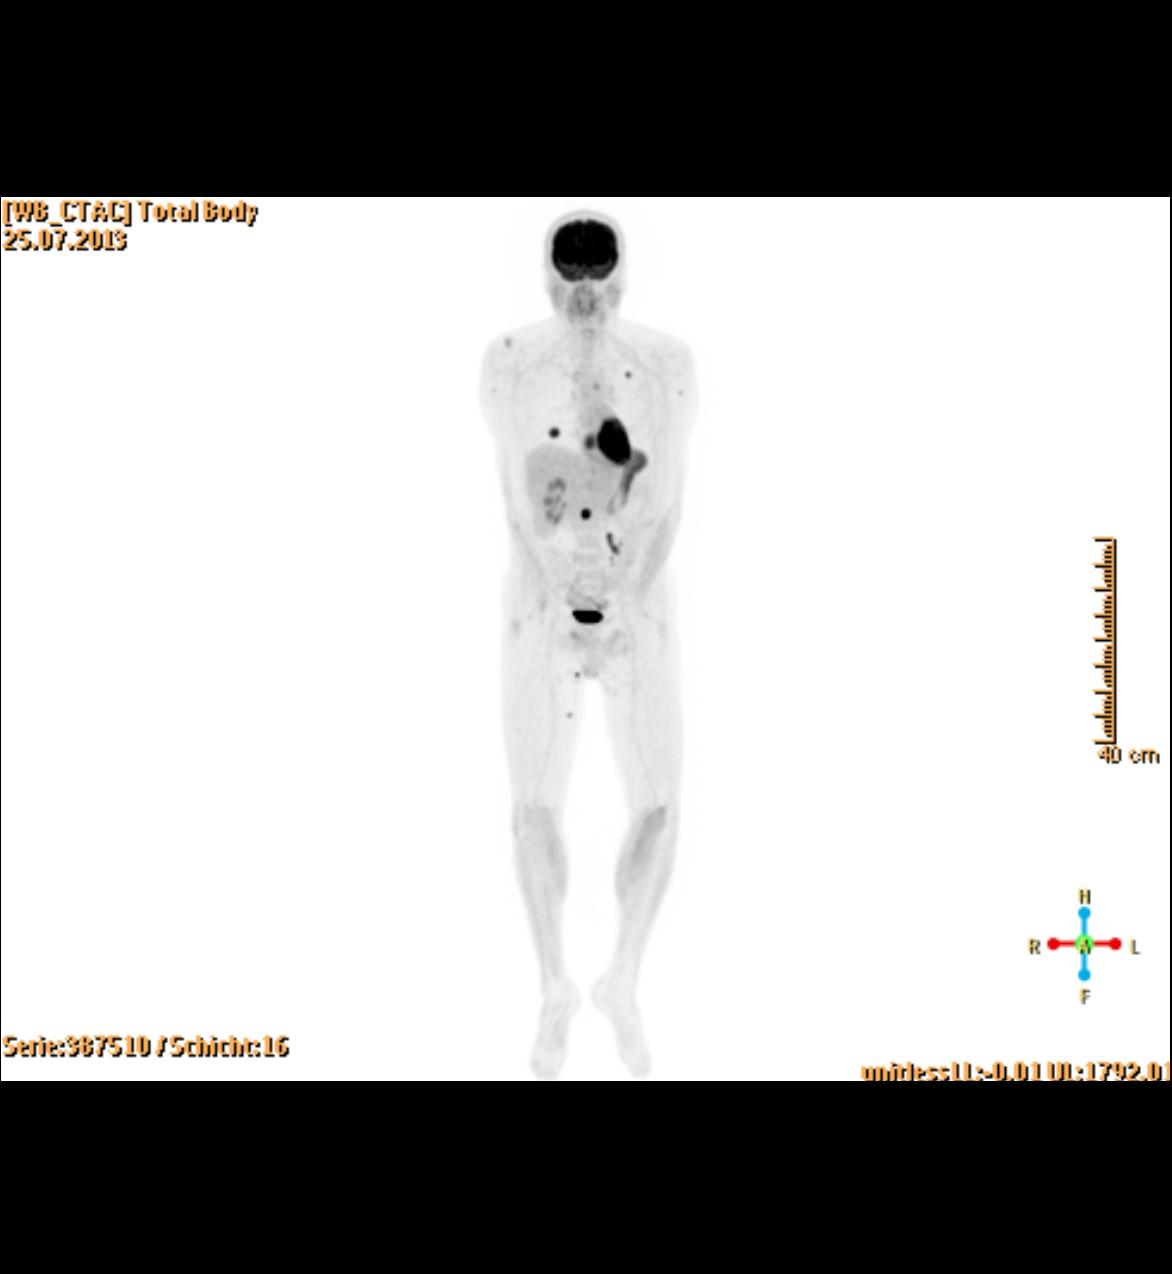

Die PET/CT ist in der Medizin derzeit die modernste zur Verfügung stehende bildgebende Untersuchung in der Diagnostik von Tumorleiden. Sie ermöglicht oft, sehr kleine Herde früher als mit anderen Verfahren wie Kernspintomographie (MRT) oder alleiniger Computertomographie (CT) zu entdecken. Ein besonderer Vorteil des Verfahrens besteht in der Kombination zweier bildgebender Verfahren, die sich perfekt ergänzen. Durch die CT Technik können Körperregionen und mittlerweile auch der gesamte Körper als vollständiger, lückenloser Datensatz erfasst werden. Dadurch entstehen Bilder in bis dahin ungeahnter Schnelligkeit und Qualität. Im PET werden im Gegensatz zum CT in erster Linie funktionelle Stoffwechselvorgänge im Körper dargestellt. Dazu wird Ihnen radioaktiv markierter Zucker (Glucose) in minimaler Menge in eine Vene injiziert. Die Verteilung im Körper wird mit einer speziellen Kamera (PET/CT-Scanner) gemessen, die Schnittbilder des Körpers gewinnt.

Die Glucose wird mit dem Radionuklid Fluor-18 markiert, das eine Halbwertzeit von 110 min hat. Das bedeutet, dass alle 2 Stunden die Radioaktivität um die Hälfte abnimmt. Zusätzlich wird innerhalb der ersten 2 Stunden ein Großteil der Radioaktivität über den Urin ausgeschieden. Insgesamt ergibt sich daraus eine durchschnittliche Strahlenbelastung von 6 mSv. Durch die PET wird also das Doppelte der natürlichen jährlichen Strahlenbelastung verursacht.

Zusammen mit der PET wird in der gleichen Untersuchung eine Computertomographie (CT) durchgeführt. Je nach Fragestellung und wenn schon Voraufnahmen vorhanden sind, wird das CT meist als Niedrig-Dosis CT ohne Röntgenkontrastmittel gefahren, d.h. mit niedriger Strahlenbelastung aber eingeschränkter Erkennbarkeit von anatomischen Details.

Ein Hybridgerät zwischen PET und CT in 64-Zeilen Technik wie am Klinikum Ludwigshafen kombiniert also in idealer Weise die detailgerechte hoch ortsaufgelöste Abbildung morphologischer und funktioneller Krankheitsaspekte insbesondere im Bereich der Onkologie.

- Nach einem Informations- und Aufklärungsgespräch spritzt der Arzt Ihnen die radioaktiv markierten Zucker in die Vene. Die Glucose muss sich in einer Ruhezeit von 50 min im Körper verteilen. Erst danach erfolgt zuerst die CT, direkt anschließend die Aufnahmen mit der PET-Kamera. Die beiden Untersuchungen zusammen dauern ca. 20 Minuten. Während der Untersuchung sollten Sie ruhig atmen und sich möglichst wenig bewegen.